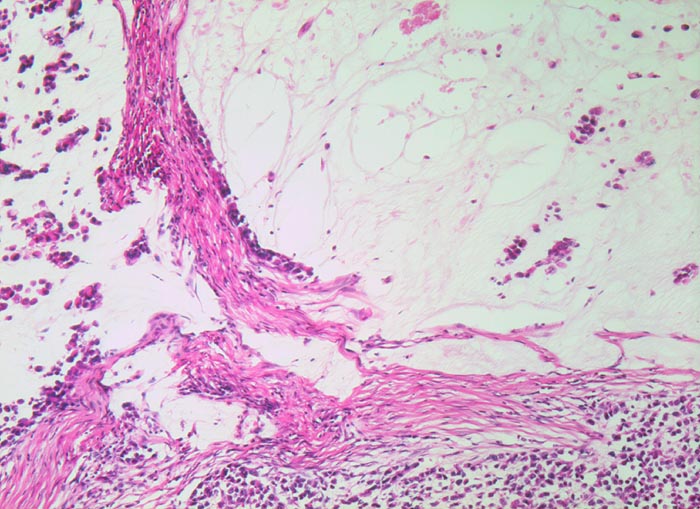

Adenokarzinom mit muzinöser Differenzierung

Stellenweise zeigt das Karzinom eine muzinöse Differenzierung mit Bildung von extrazellulären Schleimseen. Kleine Tumorzellgruppen schwimmen im Schleim. Der Schleim wird von dichtem desmoplastischem Stroma begrenzt.

Adenokarzinome können (in absteigender Reihenfolge des Differenzierungsgrades) tubuläre, papilläre, muzinöse, siegelringzellige oder gar keine Differenzierung zeigen.